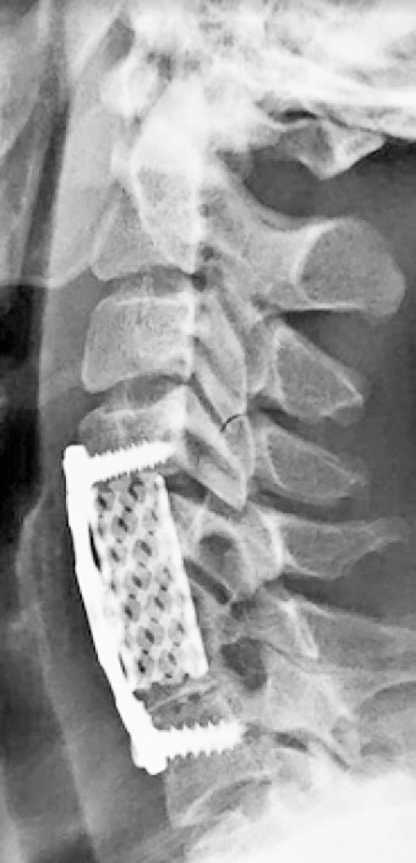

En anterior ansats är ACDF (anterior cervikal dekompression och fusion) där kotpelaren opereras framifrån, disken avlägsnas och en fusion görs mellan ovan- och nedanstående kota. Fusionen görs i regel som plattfixation med bur eller trikortikalt ben­graft. Ibland är det nödvändigt att även göra en korpektomi, där större delen av kotkroppen avlägsnas (se figur).

Postoperativ röntgen av halsryggen efter främre fusion och dekompression (ACDF). Fusionen har gjorts med platta och bur.